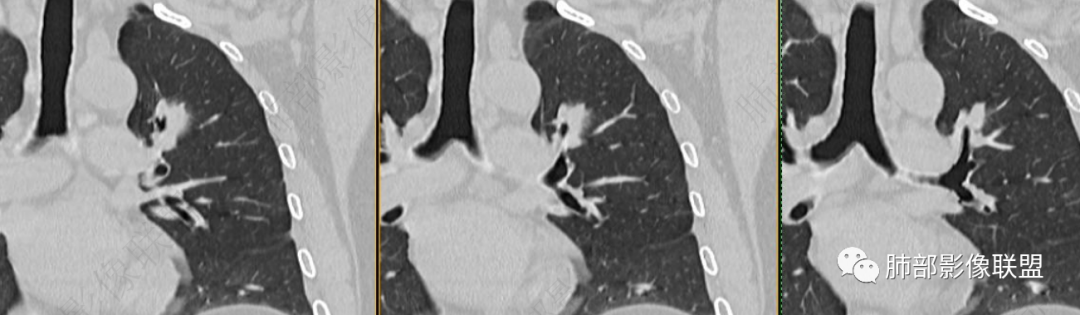

病灶朝前、外侧进展

病灶包括两部分

1、实性2、周围GGO

2、病灶以实性密度为主,前、外侧蔓延,GGO部分边界清楚,部分欠清

支气管未见受明显侵犯,未见阻塞,壁增厚,狭窄或扩张。

1、连续3年观察,病灶逐步增大,符合惰性恶性肿瘤。2、支气管壁增厚,腔内内壁无变化——病灶长轴沿支气管周围蔓延;朝外走,内侧没有,提示病灶间质为主,与支气管无关。

3、GGO长期存在,朝外蔓延,支持恶性特点。

支持淋巴瘤的关键点:1、间质为主;2、与支气管无关;3、边缘GGO的长期存在支持恶性

因为与支气管无关不支持腺癌,还是要警惕淋巴瘤。